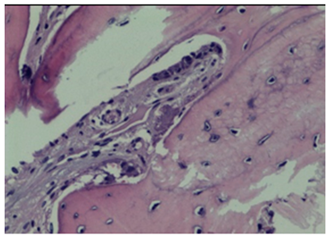

3.2. Histological Observation